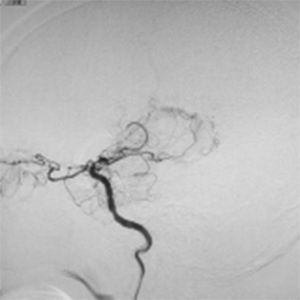

程度が軽い場合には、薬の治療(内科治療)のみを行います。程度が軽い方は、お薬だけで脳梗塞の再発を防げる場合も多いです。しかし、程度がひどい場合、脳血流が低下している場合には、お薬だけでは、2年で20%前後の人が脳梗塞の再発を起こすともいわれております。狭窄や閉塞は慢性的に詰まっており、再開通させることはできません。そのかわりに、頭皮の血管(主に、浅側頭動脈)を剥離し、頭の中の脳血管に顕微鏡を用い吻合することにより、脳の血流量を外から増やすバイパス手術を行います。浅側頭動脈中大脳動脈バイパス術(STAMCAバイパス術)といいます。バイパス術で脳の血流を増やすことにより、脳梗塞の再発する危険性を大きく減らすことできます。現在のガイドラインで推奨されている手術適応は、簡単にいうと73歳以下の比較的元気な方で、脳の血流が著しく低下している方です。最近は、平均寿命も延び、高齢な元気な方も増えております。国内、海外でも高齢者に対するバイパス手術で良好な成績を示す報告は増えております。当院でも、全身状態やほかのご病気の有無を確認し、全身状態が良い場合には、高齢者でも、十分な術前検査を行ったうえで、バイパス手術を行っており、良好な成績を出しております。

また、椎骨動脈や脳底動脈といった後方循環の病変は上記の適応に含まれず、十分なエビデンスがありませんが、内科治療のみでは再発率が高く、特に重篤な脳梗塞をきたすことがわかっております。これらの後方循環の狭窄/閉塞に対するバイパス術を技術的に難しく、成功率を高めるには豊富な経験が必要です。当院では、これらの患者さんに対して十分に精査したうえで、バイパス手術、具体的には、浅側頭動脈上小脳動脈バイパス術(STASCAバイパス術)、後頭動脈後下小脳動脈バイパス術(OAPICAバイパス術)などを行っています。